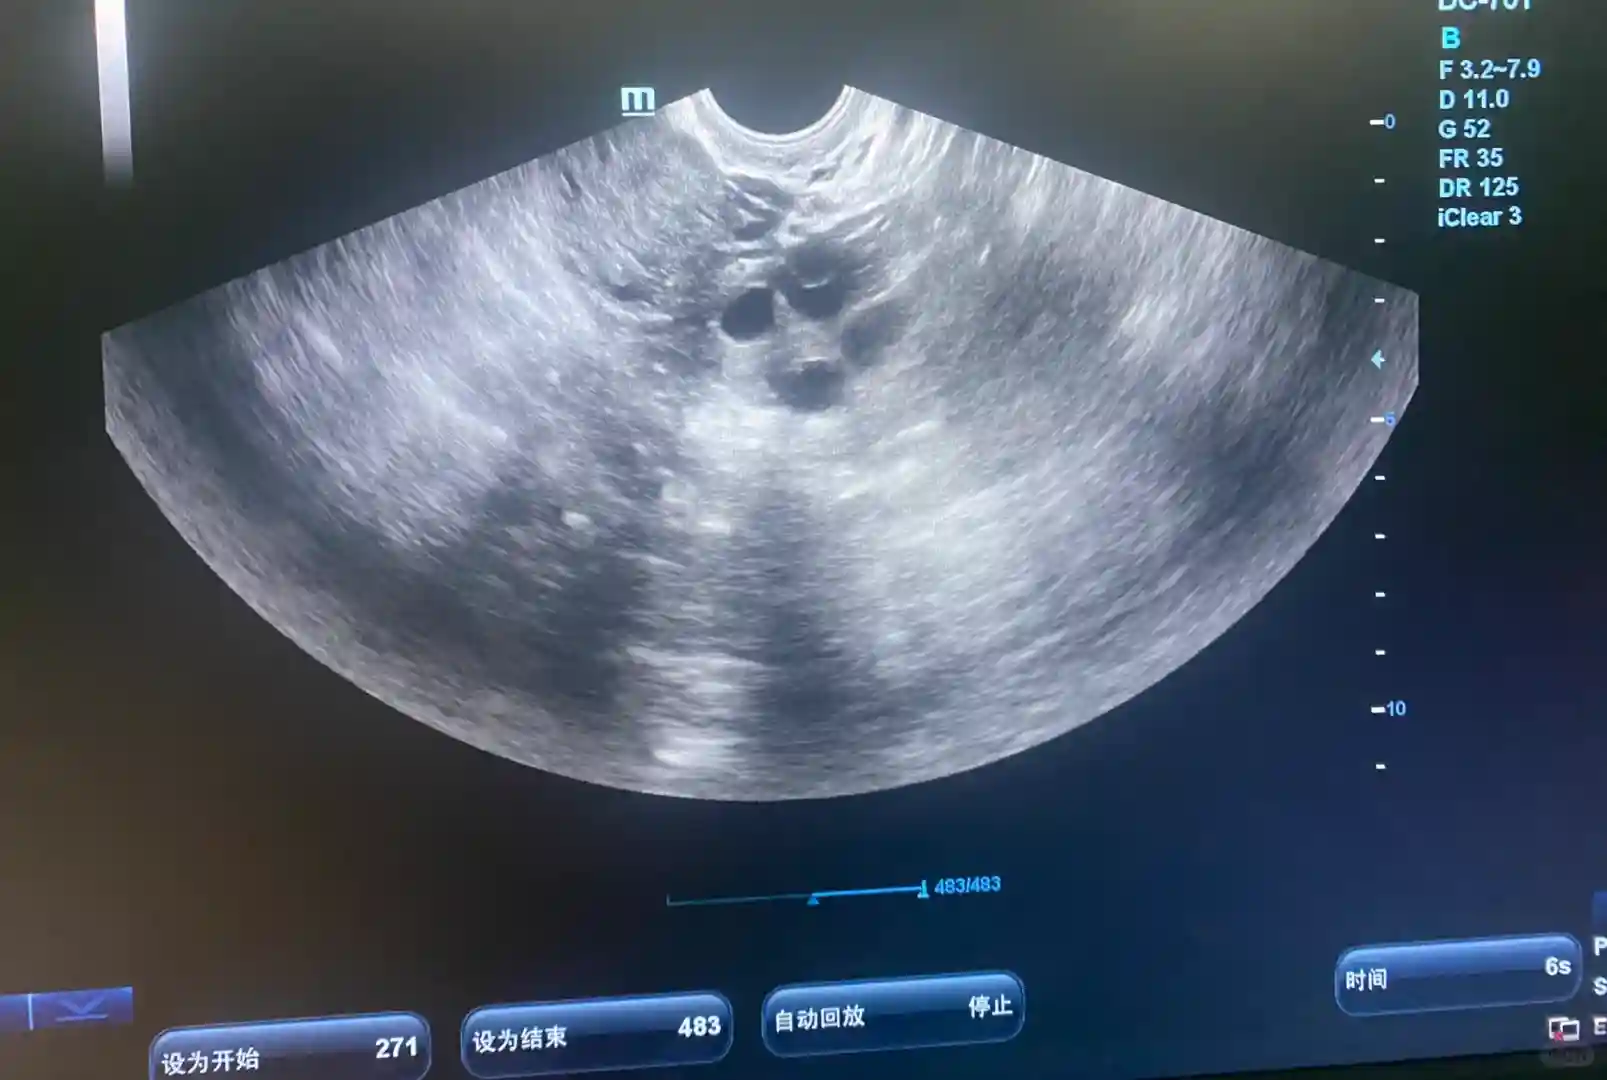

5⃣️移植后,胡主任给我开了黄体酮和肝素。看我心态良好,胡主任也依然不断地鼓励我,每次问诊检查都是在肯定我们病患所作出的努力和付出。移植后的两周,我是直接去医院验HCG得知成功怀上,第一时间就和胡主任报了喜~后面几次例行检查,hcg翻得又快又好,胡主任当即说了一句“是不是怀了双胎呀?”,当时我还不敢相信。没成想再到后面拍B超,显示有2个胎心胎芽的时候,再一次折服于胡主任的专业。